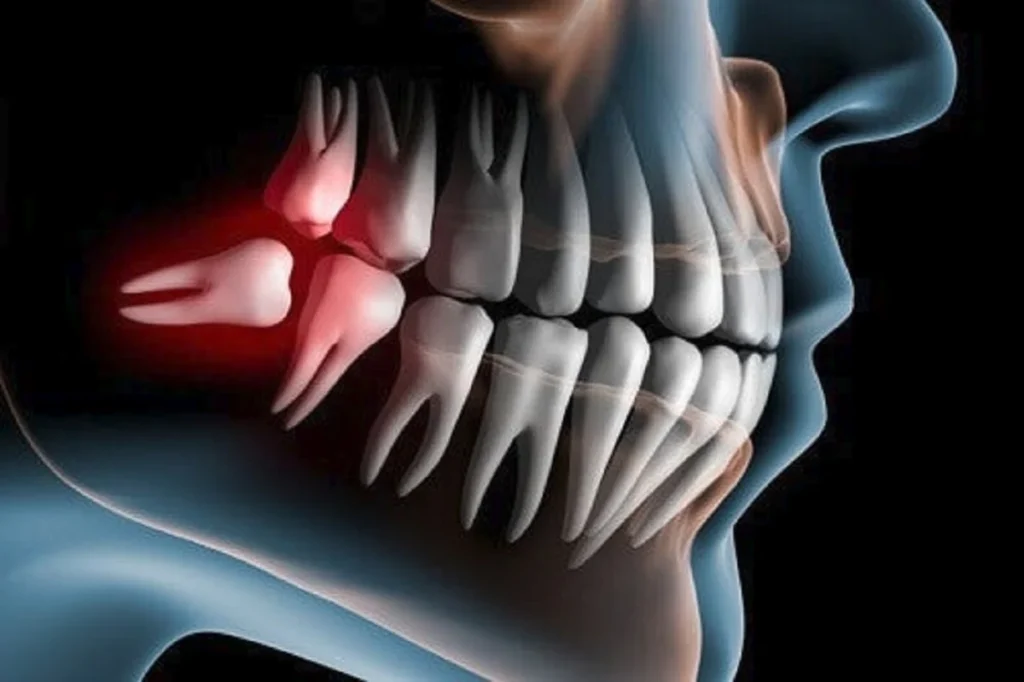

Un’infezione comune è la pericoronite, che si verifica quando un dente del giudizio spunta solo in parte e una parte della gengiva rimane sovrastante. I residui alimentari e i batteri si accumulano facilmente in quell’area, provocando:

Un dente incluso è un dente che non riesce a emergere dalla gengiva, rimanendo parzialmente o completamente intrappolato nell’osso o nella gengiva. I sintomi includono:

I denti inclusi possono anche generare cisti o lesioni ossee, che richiedono un intervento chirurgico tempestivo.